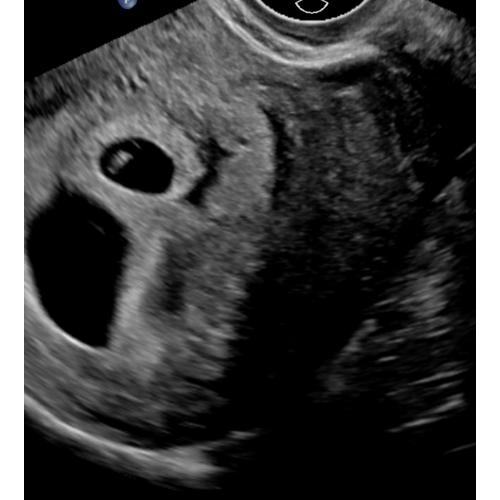

Er lopen heel wat aders enz daar langs en vergeet de placenta niet die zorgt voor bloed toevoer naar je kindje

Zou het niet een ader of iets dergelijks kunnen zijn?

Zou het geen ader kunnen zijn van jou? Dat zie je geloof ik ook kloppen